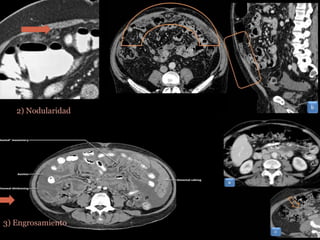

 Hallazgos:

1) Ascitis

2) Nodularidad

3) Engrosamiento

CARCINOMATOSIS MUCINOSA  +Frecuente .  Secundario : Ovario, TGI , mama, pulmón y melanoma.  Diseminan : Directa. Linfática. Intra-peritoneal. Hematogena.  Hallazgos: 1) Ascitis